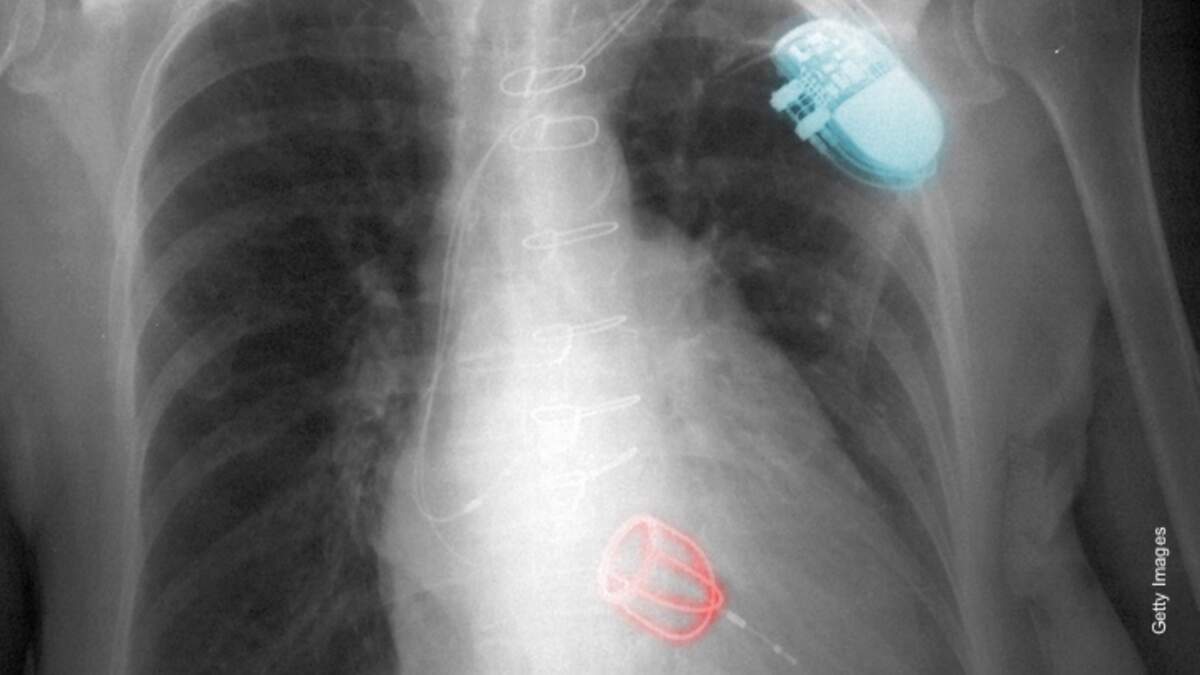

In the second half, writer Michael Fitzhugh Bell updated his story of being drugged, abducted, and surgically implanted with microchips. He says that he has the actual medical photos, X-rays, ultrasound and MRI images, all showing non-therapeutic tracking and torture devices. His saga began when he was abducted from his apartment in Hollywood, California and woke up eight days later with unexplained scars all over his body. He concluded that he was "probably part of a massive clinical field test" of mind control and behavior modification devices which he refers to as "implanted nanotechnology." He believes a car accident in his teen years in which he was traveling with the child of a wealthy family may be the source of his troubles, with revenge as the motivation.